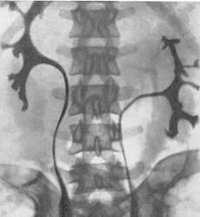

Удвоенная собирательная система – термин предполагает наличие двух чашечно-лоханочных систем с одним или двумя мочеточниками. Последние могут сливаться по пути к мочевому пузырю. Удвоение может быть одно- или двухсторонним. Удвоенная почка увеличена в размерах, иногда сочетается с аномалиями поворота и гидронефрозом. Экскреторная урография надежно визуализирует данную аномалию развития.

Экскреторная урография. Полное двухстроннее удвоение мочеточников.

Торакальная дистопия диагностируется при проведении профилактической флюорографии или обзорной рентгенографии грудной клетки. Дистопированная почка чаще определяется как плотная округлая тень в заднем средостении над диафрагмой. Для правильной диагностики патологии и определения формы заболевания применяются визуализирующие урологические методы – УЗИ почек, ретроградная и экскреторная урография, радиоизотопная ренография (сцинтиграфия), почечная ангиография, МРТ, МСКТ почек.

УЗИ почек позволяет определить отсутствие почки на своем анатомическом месте и дифференцировать дистопию с нефроптозом. Экскреторная урография, как правило, точно выявляет аномальную локализацию почки, степень ее ротации и ограниченную подвижность. При резком снижении функции почек выполняется ретроградная пиелография. В ходе почечной ангиографии устанавливается уровень отхождения почечных артерий от ствола аорты. Дифференциальную диагностику аномалии проводят с нефроптозом, опухолями почки, кишечника, придатков.

- Рентгеновские методики. С помощью экскреторной урографии определяется количество почек, их локализация, структура. Часто при агенезии отсутствует также соответствующий мочеточник и треугольник Льето, иногда устье и нижняя треть мочеточника остаются сохранными. Более точную картину дают почечная ангиография, КТ/МРТ забрюшинного пространства, нефросцинтиграфия.